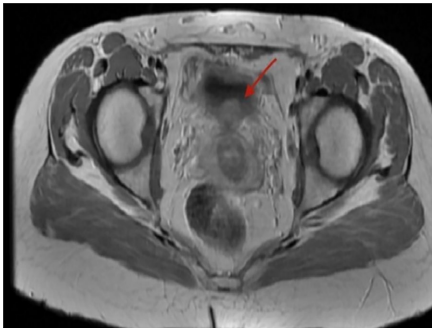

研究团队采用了循序渐进的诊断策略:首先通过实验室检查排除常见泌尿系统疾病,发现患者存在明显血尿(显微镜下满视野红细胞)和国际标准化比值(INR)2.5的凝血异常。影像学检查成为关键突破口,超声(US)初步发现膀胱后壁占位,计算机断层扫描(CT)精确定位到一个3cm的肿块,磁共振成像(MRI)则进一步显示病灶在T2加权像上的特征性低信号表现。尽管膀胱镜(Cystopanendoscopy, CPE)和诊断性腹腔镜可能提供更多信息,但基于影像学的高度特异性表现,团队决定直接进行手术治疗。

在Discussion部分,作者系统回顾了膀胱子宫内膜异位症的特征:84%的泌尿系统子宫内膜异位症发生在膀胱,且60%病例症状与月经周期无关——这与本病例完美契合。关于发病机制,作者讨论了种植学说(Implantation theory)、体腔上皮化生学说(Celomic metaplasia theory)等多种假说,但均无法完全解释所有临床表现。诊断方面,强调MRI高达98%的准确率使其成为深部浸润型病变的首选,而腹腔镜(Laparoscopy)仍是金标准。治疗策略上,作者比较了药物疗法(如GnRH激动剂)与手术切除的优劣,指出对于膀胱浸润病例,彻底切除病灶(即使需要打开膀胱)是关键。